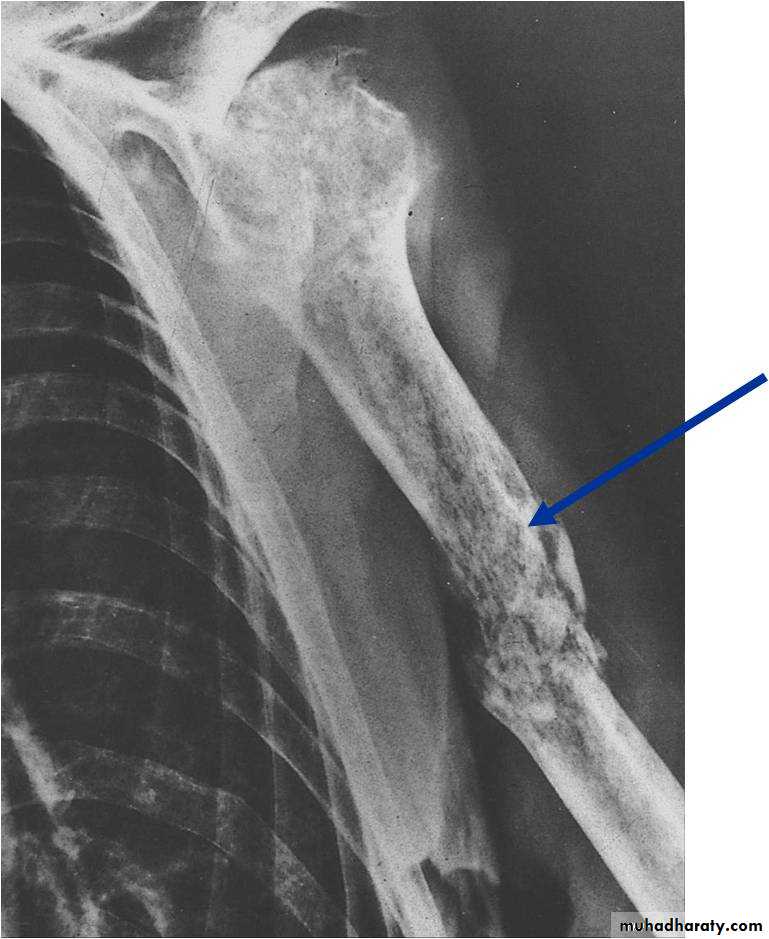

Radiography

* Early is negative only soft tissue swelling.* After 2 weeks will shows rarefaction of the bone

* After 3 weeks new bone formation ( periosteal new bone formation )( involucrum)

3. Pathological fracture.

Pathological fractureComplications